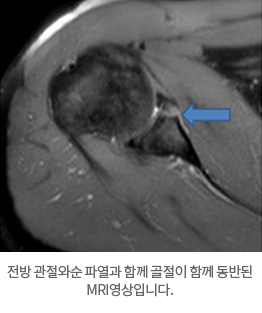

재발성탈구가 되면 MRI 등으로 관절순 또는 인대들의 상태를 분석하는 것이 필요합니다. 또 하나 재발성 탈 구시 골절을 동반하는 경우와 골 결손이 심하면 수술 전 CT사진이 필요합니다.

전방 관절와순 파열과 함께 골절이 함께 동반된 MRI영상입니다.